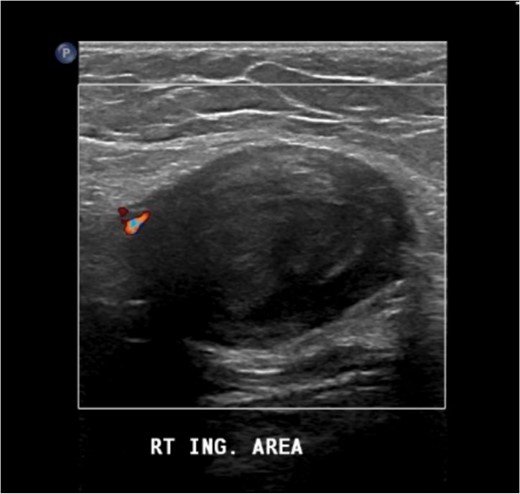

The US image revealed a well-defined hypoechoic heterogeneous echotexture mass lesion measuring 4.1 × 2.7 × 3.5 cm in the right inguinal area, with minimal peripheral vascularity in color flow Doppler. An adjacent normal inguinal lymph node was seen (Fig. 1).

The US image revealed a well-defined hypoechoic heterogeneous echotexture mass lesion seen in the right inguinal area.